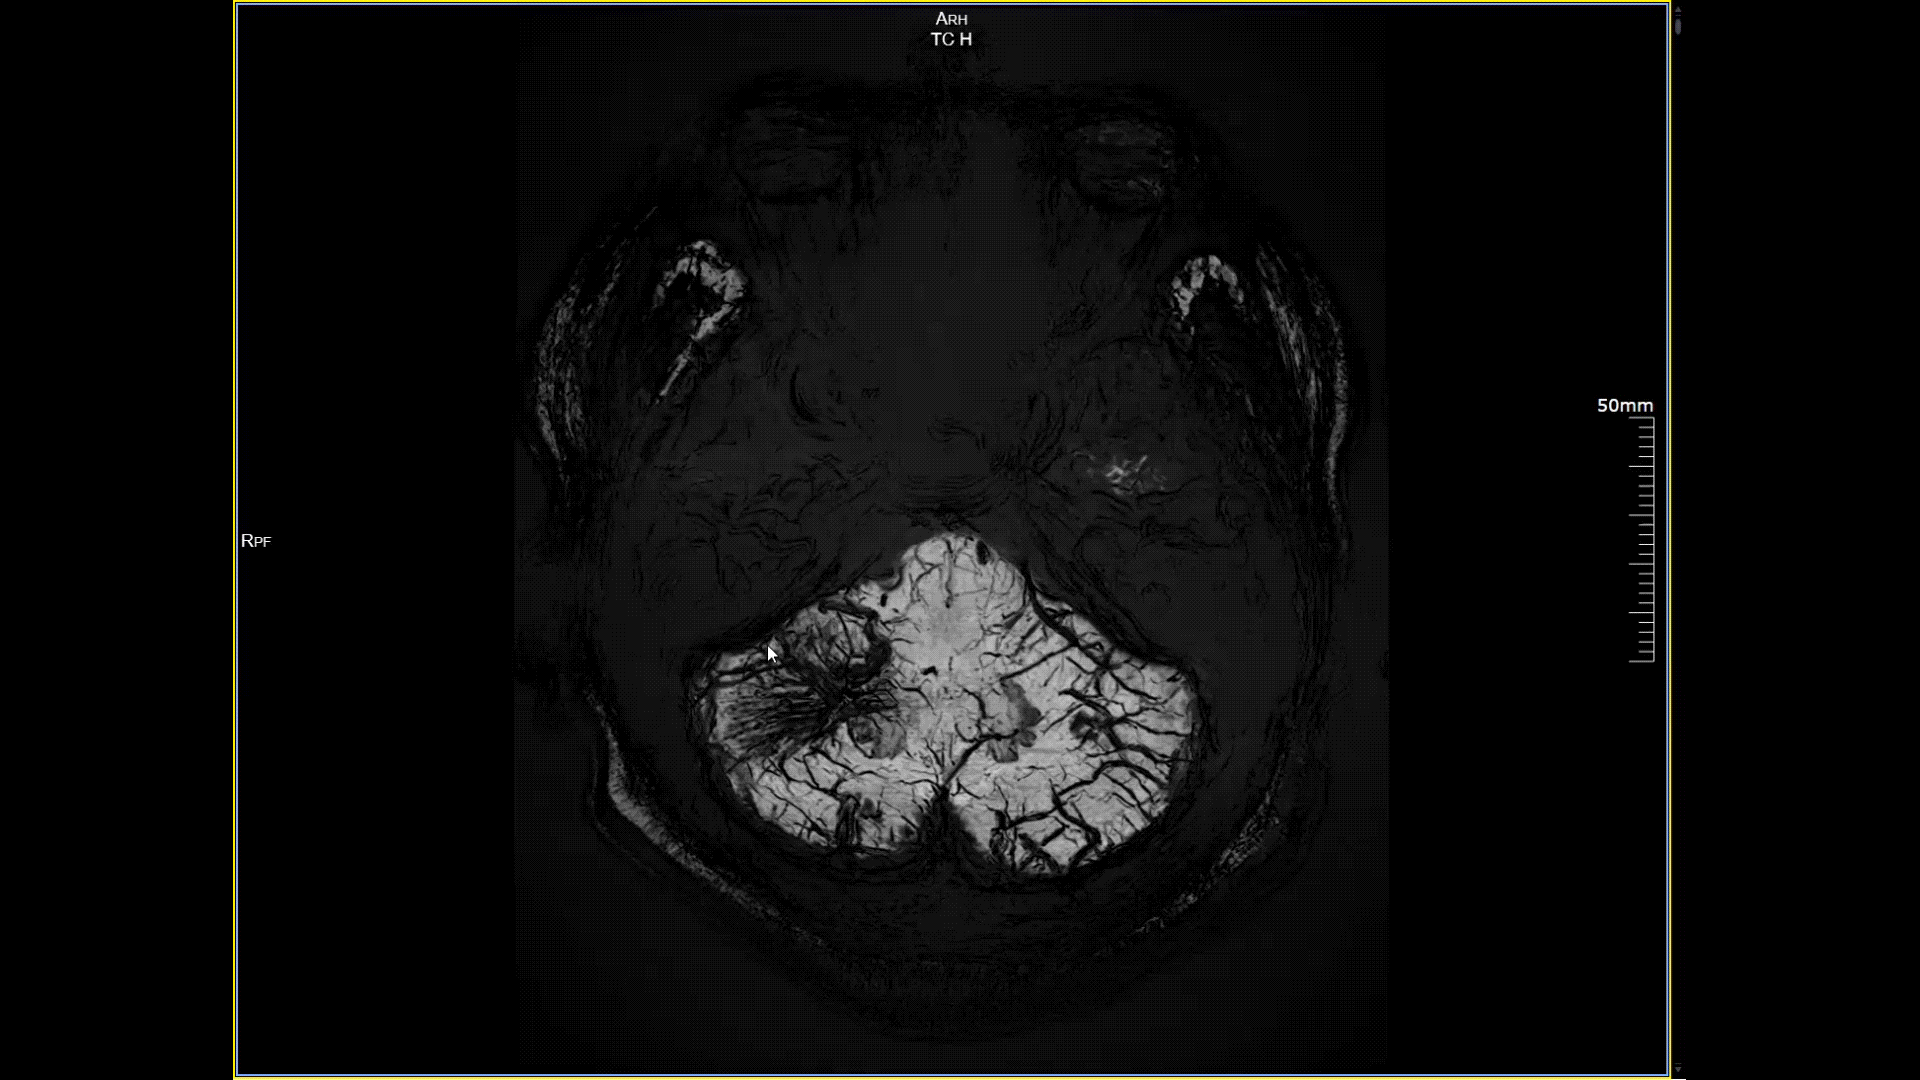

11月3日,一名30岁男性在我院接受了河北省首台5.0T超高场核磁共振头颅血管成像检查,图像清晰精准地反映出患者右侧小脑区域的血管畸形情况,该患者对我院的诊疗实力与服务温度给予充分肯定。相较于传统核磁共振,这台设备实现了“超高场全身各部位成像”的技术突破,它以业界领先的超高性能实现亚毫米级超高清成像,尤其在神经、心血管、体腹、关节等部位肿瘤疾病的早期发现、精准评估、个性化治疗方案制定中提供了的强大影像支持,将为全省乃至周边地区患者带来更优质、更精准的医疗服务。

5.0T磁场强度远高于其他设备,使得氢原子核在磁场中的响应信号极大地增强。这就像在安静的房间里能听清细微的声音一样,高信噪比能让医生看到更微小、更模糊的病变结构。例如上述患者的检查,该设备可以呈现0.2x0.2毫米高分辨率的图像以及动态显示血管走行,使得病变血管的细微解剖结构、分布及其与周边脑组织的关系得以直观呈现,为临床医生进行精准诊断并制定后续治疗方案提供了重要的影像学依据。

磁敏感成像SWI,分辨率0.2*0.2mm